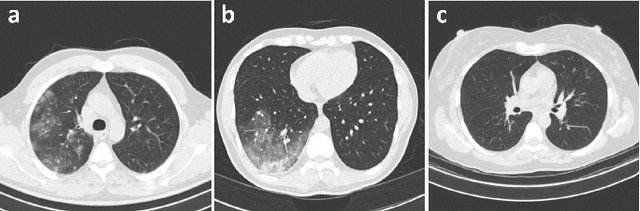

Abstract:Computed tomography (CT) has been widely explored as a COVID-19 screening and assessment tool to complement RT-PCR testing. To assist radiologists with CT-based COVID-19 screening, a number of computer-aided systems have been proposed; however, many proposed systems are built using CT data which is limited in both quantity and diversity. Motivated to support efforts in the development of machine learning-driven screening systems, we introduce COVIDx CT-3, a large-scale multinational benchmark dataset for detection of COVID-19 cases from chest CT images. COVIDx CT-3 includes 431,205 CT slices from 6,068 patients across at least 17 countries, which to the best of our knowledge represents the largest, most diverse dataset of COVID-19 CT images in open-access form. Additionally, we examine the data diversity and potential biases of the COVIDx CT-3 dataset, finding that significant geographic and class imbalances remain despite efforts to curate data from a wide variety of sources.